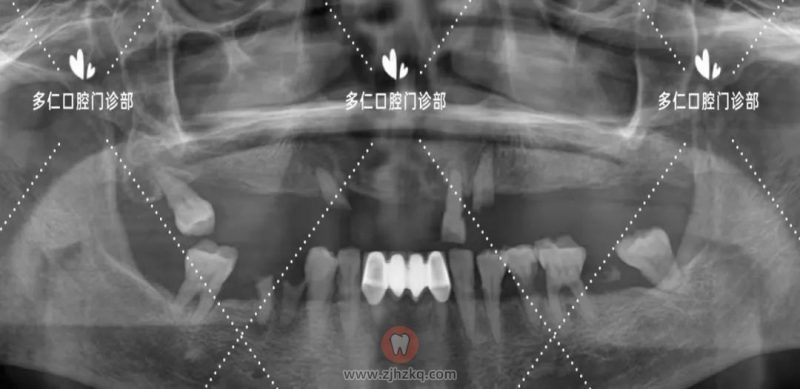

术前CBCT